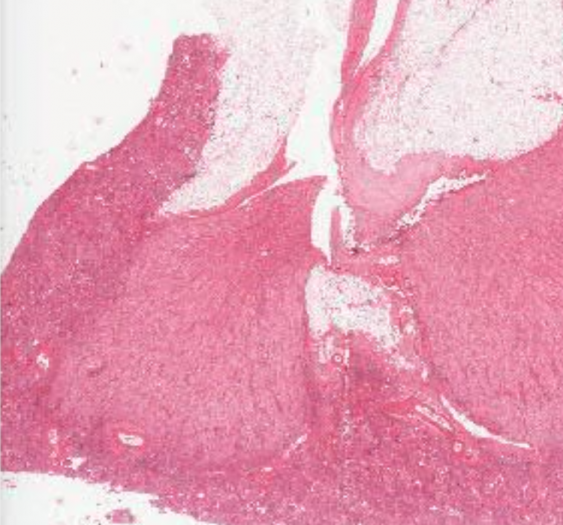

细胞和组织的适应与损伤

宫颈表皮样化生